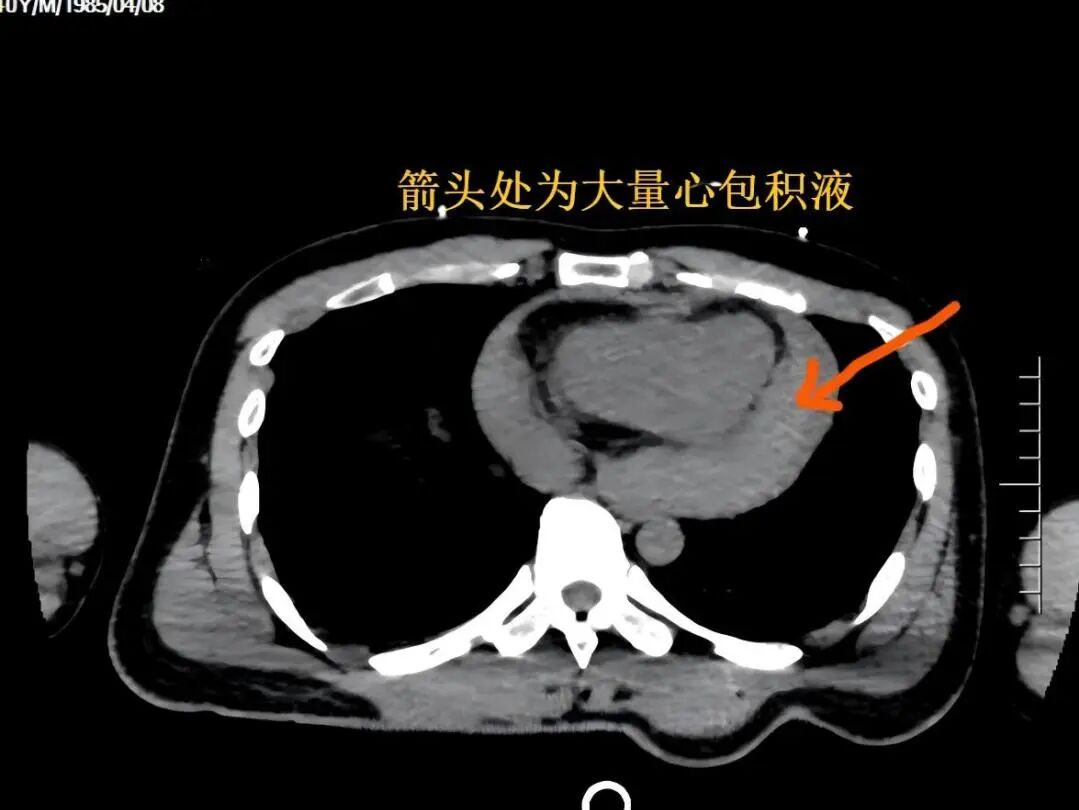

评估到该患者随时可能因心脏骤停而失去生命,急诊科胡瑞华副主任医师立即开启绿色通道为患者完成胸腹部增强 CT 检查,检查结果很快出来——心包积液,考虑为心包撕裂出血引发的急性心包填塞。这是一种致命急症,因心脏外层的心包内短时间积聚大量血液,压迫心脏导致泵血功能骤降,正是患者休克的核心元凶。

常规的穿刺点有两个:一是剑突与左侧肋弓夹角处,可以直接到达心包底部,并且可以避免气胸的风险;另外一个是左侧第 5 肋间隙,心浊音界左缘向内 1-2 cm 处,也可以避免气胸的风险。然而,经过超声医学科医生定位检查,这两个常规点位竟没有明显积液,积液大量聚集在稍远的心尖部位。但是此处邻近肺组织,这意味着,稍有不慎就可能刺伤肺部引发气胸,让本就危急的病情雪上加霜。